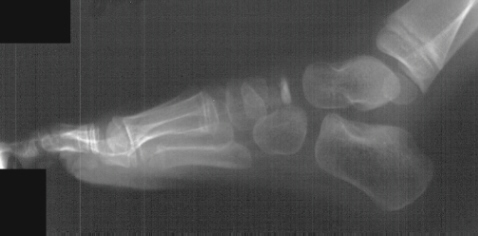

This patient is a six year old male with a three week history of right

foot pain. The mother and patient relate no history of trauma. Patient

came home from school three weeks ago with pain and swelling over the medial

aspect of the right foot. Symptoms have persisted for past three weeks.

Mother states patient has been ambulating with a limp. There is tenderness

to palpation and minimal swelling over the medial aspect of the right navicular.